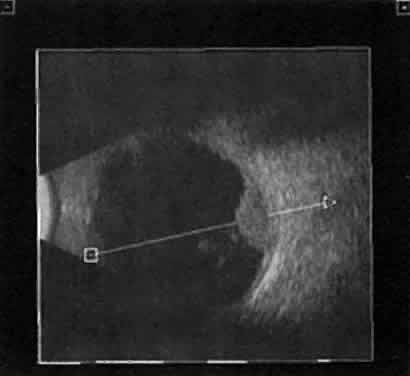

Choroidal malignant melanoma, perhaps the most widely studied intraocular mass lesion, has the most reproducible and reliable A-scan pattern. Usually, the initial echo seen in A-scan is a high-amplitude spike secondary to the strong vitreoretinal surface echo overlying the tumor mass. Once the examining sonic beam has passed into the tumor tissue, a rapidly declining amplitude cadence is noted, a consequence of increasing ultrasonic tissue homogeneity. Clinical knowledge of the typical microscopic tumor pattern of tightly packed, homogeneous small cells makes anticipation of relatively low reflectivity possible (Fig. 10). This same low-amplitude reflectivity in B-scan imaging produces a picture that makes the melanoma mass appear hollow. Often, tumor-infiltrated choroid also appears dark (Fig. 11). This change in the normally highly reflective choroidal tissue is widely but inaccurately called choroidal excavation. The terms “hollowing” and “choroidal excavation” are misleading because these tumors are not hollow and the choroid is not excavated. Nevertheless, these terms have been used so frequently in past literature that any change in vocabulary is unlikely.

Fig. 10. Contact B-scan and simultaneous A-scan: choroidal malignant melanoma. Note the strong initial echo from the overlying retinal tissue, followed by a rapid decline in A-scan echo amplitude within the deeper tumor tissue, a consequence of increasingly homogeneous tissue. High reflectivity is again seen at the level of the sclera and orbit.